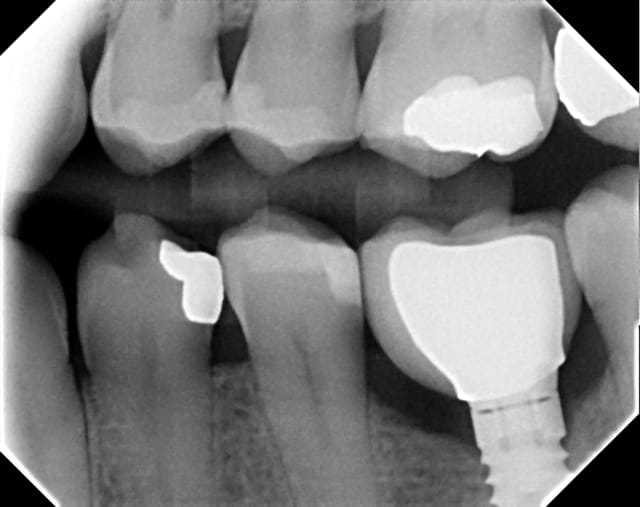

Contrôle post-op 2 ans.... reformation osseuse....

les 2 dernières radiographie sont inversées pour l'ordre chronologique

Avril2010 z0go6l - Eugenol